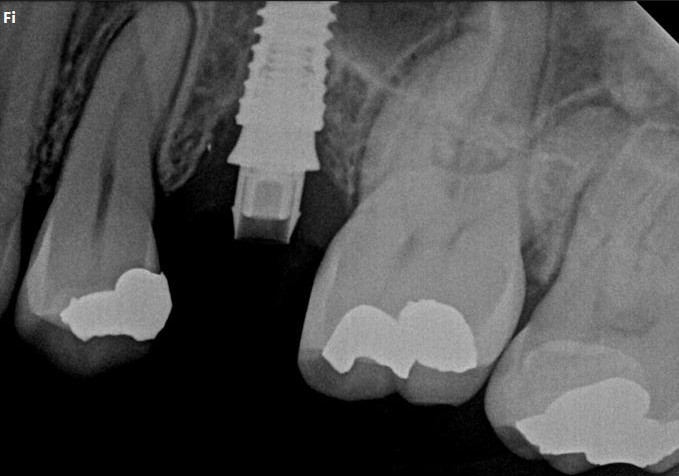

Clinical and radiographic examination revealed a failed implant with signs of periimplant tissue compromise. Intraoral evaluation demonstrated inadequate soft tissue quality and unfavourable conditions for immediate restoration. CBCT imaging was performed to assess bone volume, implant position, and anatomical limitations prior to treatment planning.

Final radiographic evaluation confirmed proper implant positioning and bone stability.